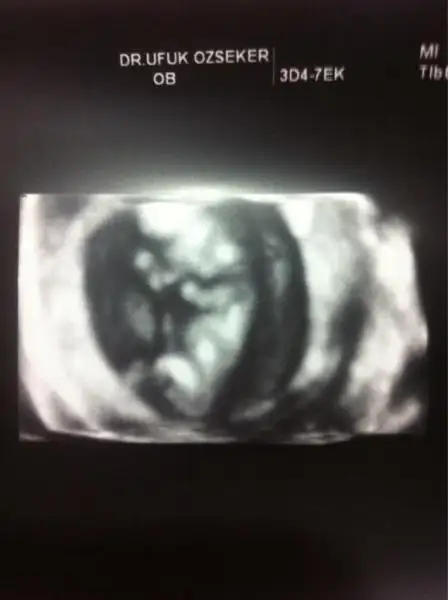

dr soylemeden siz gorun genital nub teorisi ( bebegin cinsiyeti)

Valla canm sudecete doktor erkeğe benzio demisti kesin bisi.dmedi.erkege benzio dmissinz bbana % 99 dedi kesinlesti erkek öylesine buraya attim resmi kiz dediler nub teorisi olabilir ama.snrm doktrlar daha iyi anliyor bundan

Tabi tabi hiç önemi yok merak bizimki işte :) 11+4 de %70 kız dedi 13+4 te yüzde 99 erkek oldu:) 14+2 yiz bugün farklı dr.a gittim kesin erkek dedi canım..sen kaçıncı haftadasın???

Erken haftalarda tahmin bence doktorlarinki ben 15 haftada ggtim kesin erkek çıktı ozman tam net anlaşılıyor zaten acele etmeyin cnsyet icin en az 14 hafta dolsun